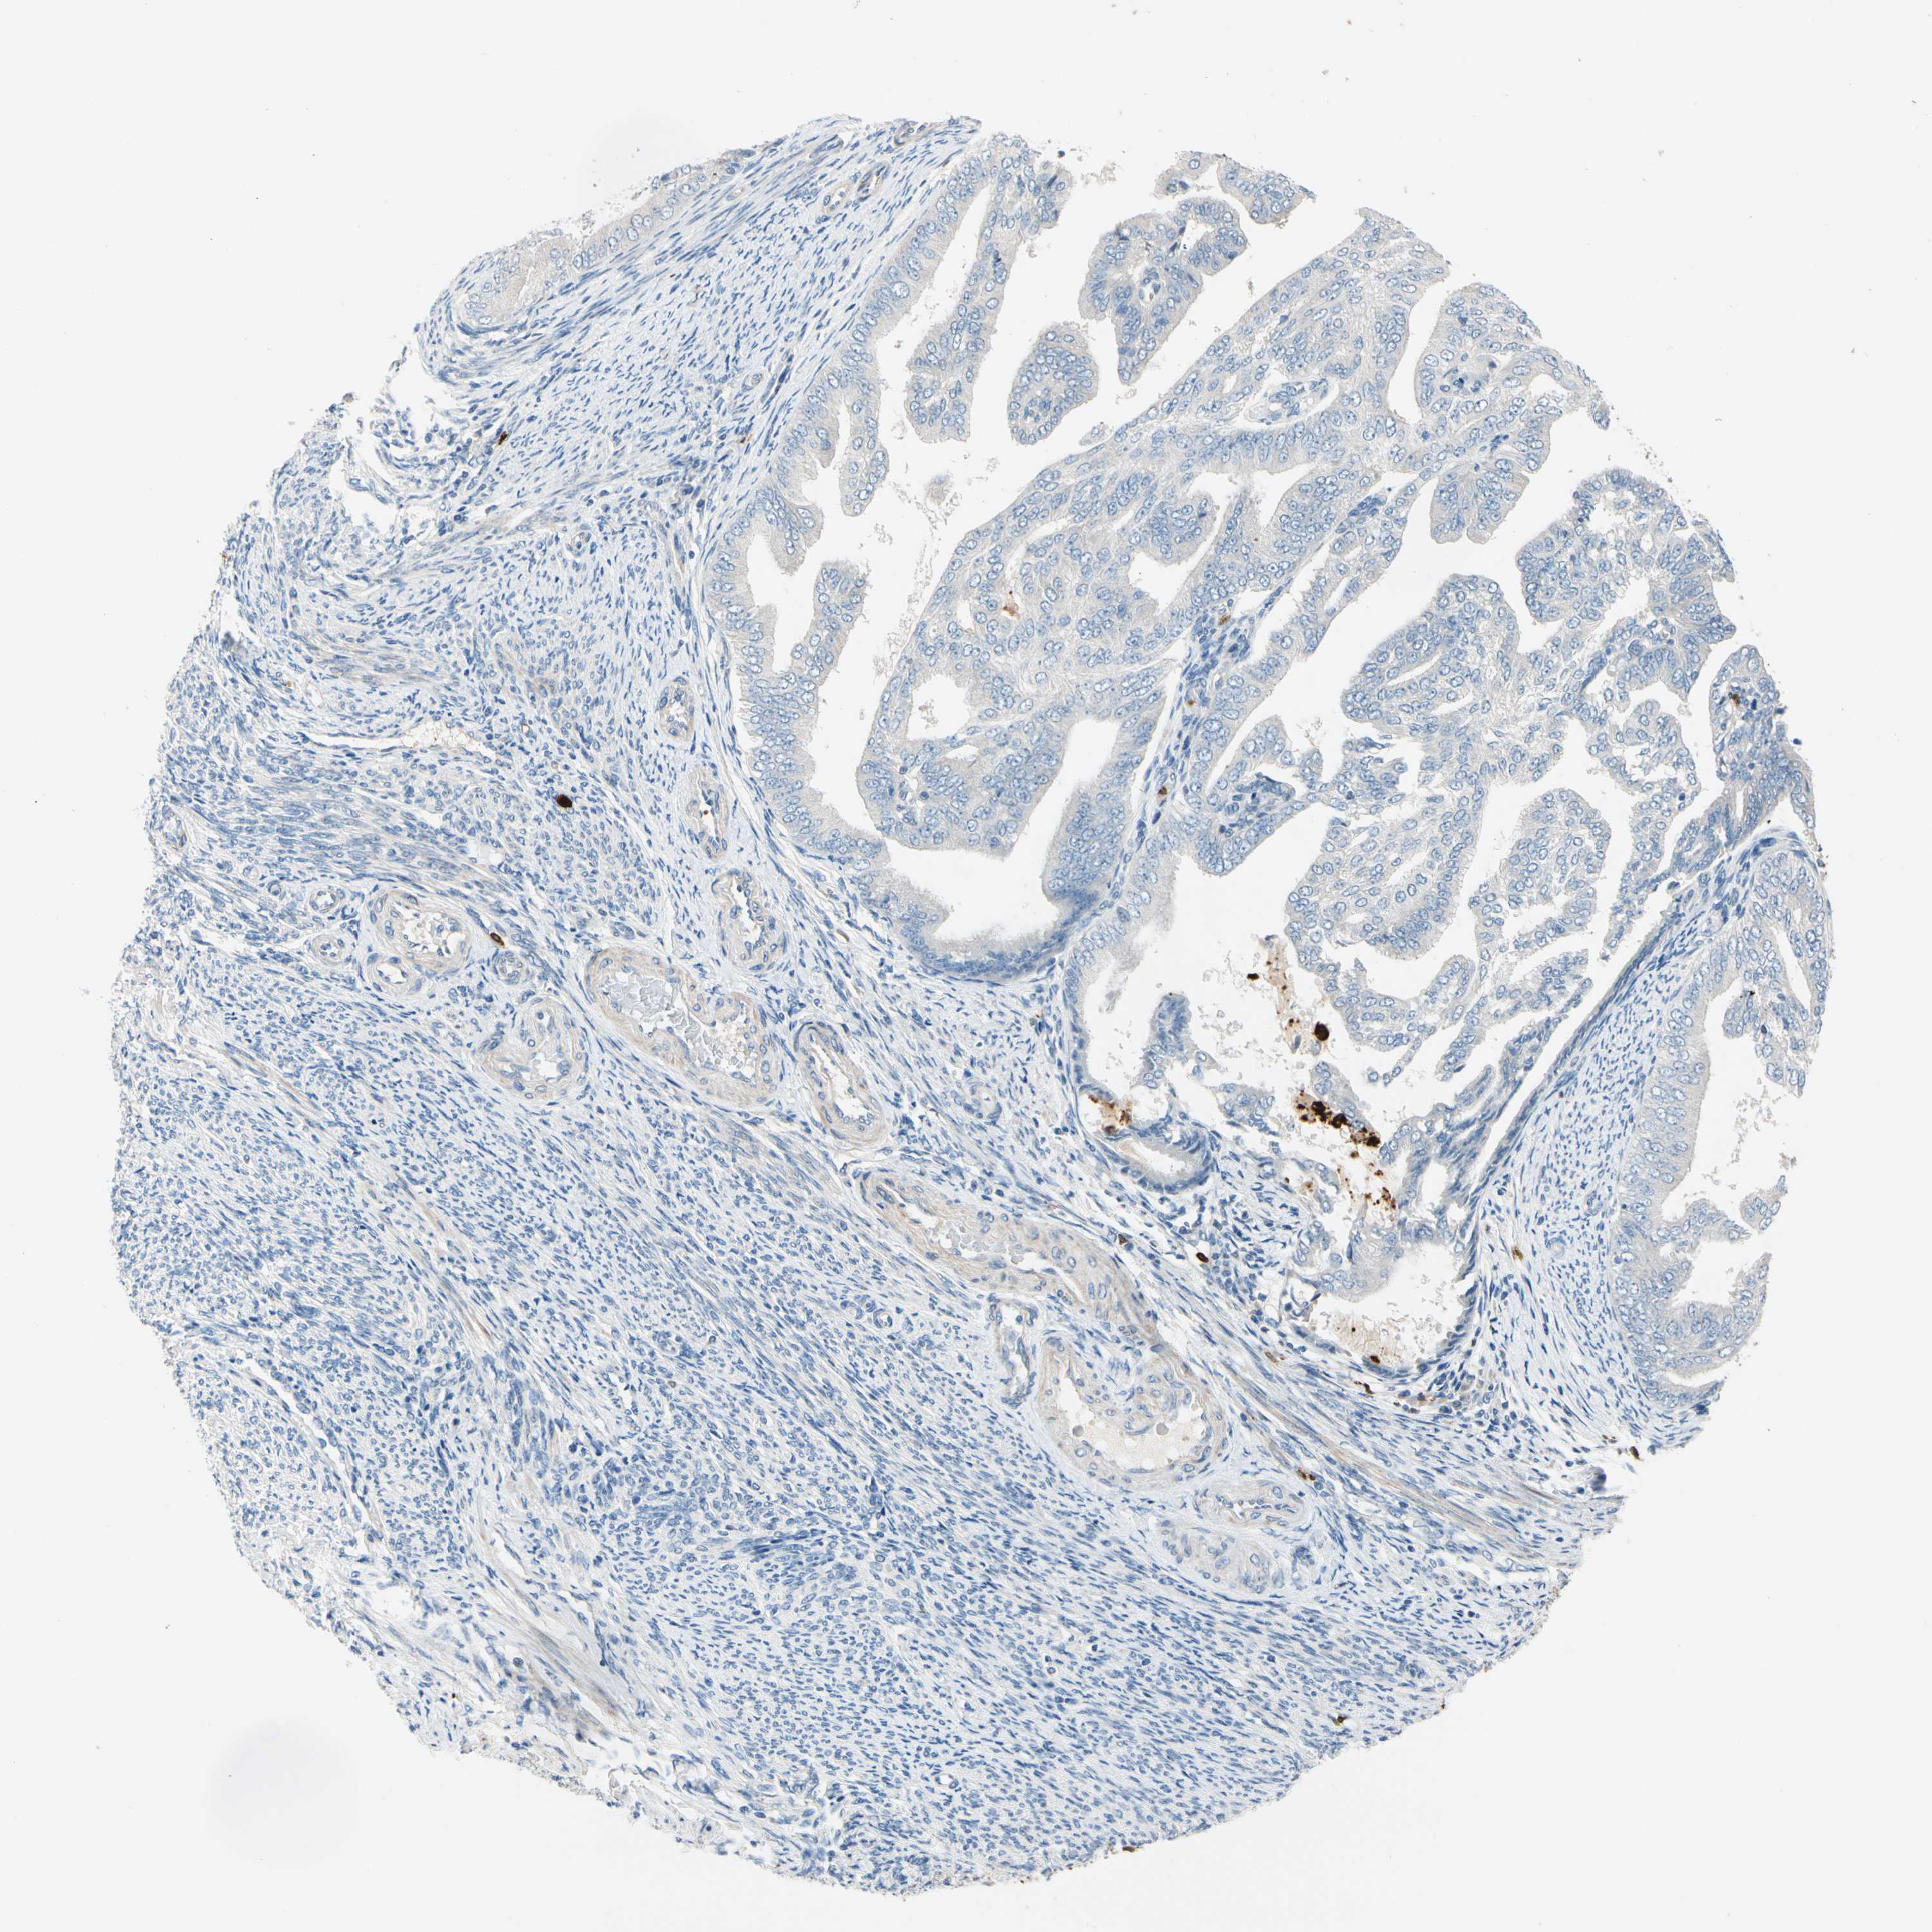

ENDOMETRIAL CANCER - Protein expressioni

A mouse-over function shows sample information and annotation data. Click on an image to view it in a full screen mode. Samples can be filtered based on level of antibody staining by selecting one or several of the following categories: high, medium, low and not detected. The assay and annotation is described here.

Note that samples used for immunohistochemistry by the Human Protein Atlas do not correspond to samples in the TCGA dataset.

Antibody stainingi

Antibody staining in the annotated cell types in the current human tissue is reported as not detected, low, medium, or high, based on conventional immunohistochemistry profiling in selected tissues. This score is based on the combination of the staining intensity and fraction of stained cells.

Each image is clickable and will lead to virtual microscopy that enables deeper exploration of all samples and also displays staining intensity scores, fraction scores and subcellular localization as well as patient and tissue information for each sample.

Antibody HPA008052

Antibody CAB010277

Staining

High

Medium

Low

Not detected

Intensity

Strong

Moderate

Weak

Negative

Quantity

>75%

75%-25%

<25%

None

Location

Nuclear

Cytoplasmic/membranous

Cytoplasmic/membranous,nuclear

Adenocarcinoma, NOS